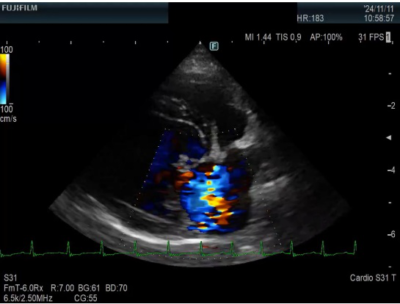

心臓超音波検査は技術を要する検査の一つであり、一般的には難しいとされていますが

当院には経験豊富な獣医師が所属しており、詳細な検査が可能です。

※逆流があるエコー写真です。黄色の所が逆流を認める箇所です。